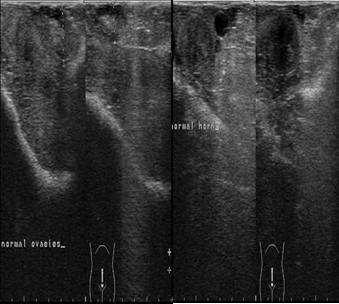

The ultrasonographic imaging of the uterus and ovaries was performed daily 9th day postpartum then followed by examination twice weekly until the 21st day postpartum. The ultrasound examination showed normal uterine involution and no abnormal secretions in the uterus (Figure 2).

Figure 2.Ultrasonographic image of ovaries (a) and uterine horn (b) at the 9th day postpartum in female camels, the image illustrate normal ovarian structure with no ovarian cysts and the uterus showed normal uterine involution and no abnormal discharges.

The serum progesterone level decreased sharply after parturition during the 1st, 3rd and 9th days postpartum, which is considered physiological decrease due to the lysis of corpus luteum of pregnancy and the drop of placenta which is considered another source of progesterone to maintain pregnancy, in addition the lactation status significantly affects on serum progesterone level16. It was proved that the plasma concentration of progesterone was increased by the 5th days after mating and remained high throughout most of pregnancy, and it starts to decline by the 2nd weeks before parturition3, 17. In addition, the low level of progesterone detected in the 1st day postpartum concur with previous studies during postpartum females in camels18 and other species19. Similar changes in the hormonal levels were observed during pregnancy, parturition and postpartum in llama20, 21. The ultrasonographic examination was performed twice weekly during the postpartum period starting from the 3rd day postpartum until the 21st day postpartum, there was normal uterine involution and no abnormal secretions in the uterus, this was in agreement with previous studies by Abu-Seida22, Derar, Ali23, who found that the uterine involution was completed in female camels from 25th until 30th days postpartum.